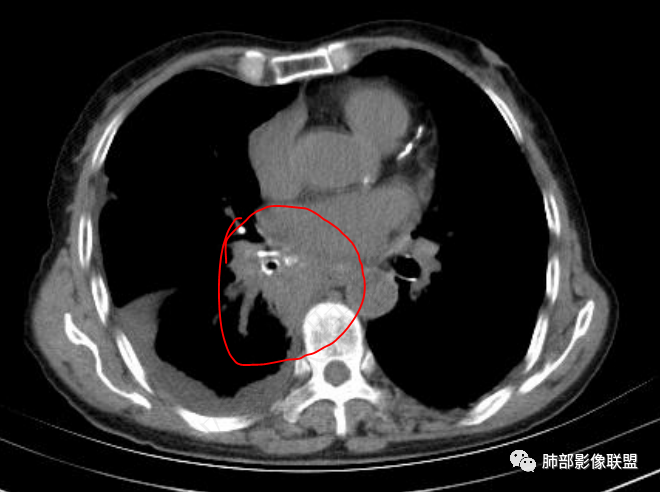

老年女性,肺气肿背景。腹痛、便血入院。右肺下叶脊柱旁软组织肿块,强化不均匀,中心有坏死,纵隔及双侧肺门多发肿大淋巴结、有融合,右下支气管周围为主,包绕支气管生长,且管壁增厚伴环形钙化、狭窄,增强后有环形强化。右侧胸膜见结节灶,增强后明显强化;右侧胸腔积液。考虑:右下肺恶性肿瘤伴纵隔、肺门多发肿大淋巴结,胸膜转移,低分化腺癌?Ca125明显升高,老年女性 是否有妇科恶性肿瘤?黏液腺癌 肺内、纵隔转移?

双肺间质性改变,右肺下叶支气管环形增厚,支气管变窄,周围见钙化影,右肺下叶软组织占位,明显的坏死,明显环形强化,两侧肺门及气管隆突下淋巴结肿大。右侧胸腔积液,肝脏周围少量腹腔积液,老年女性患者腹痛便血,Ca125明显增高。考虑1一元论:腹腔恶性肿瘤(胃肠道或卵巢来源)肺内及胸膜腹膜转移;2二元论:右下肺粘液表皮样癌/腺样囊性癌,腹腔胃肠道或卵巢来源肿瘤。

女,69,腹痛、便血4小时。CA125增高。胸部CT:肺气肿背景。右下叶不规则肿块影,处于外周气肿带与正常肺交界区,强化不均匀,中心有坏死;纵隔及肺门多发肿大淋巴结、融合,包绕支气管,部分钙化、环形强化;右下支气管周围管壁增厚伴环形钙化、狭窄。右侧胸膜多发结节灶,增强后明显强化,右侧胸腔积液。考虑恶性,右下肺腺Ca多发转移?转移瘤?鉴别TB、IgG4等。

右下肺肿块,其内坏死边界不清,边缘轻度强化,可见引流支气管,管壁增厚,冰冻肺门,内见斑点状钙化,中间支气管变窄呈针孔样,可见环状强化及血管浸蚀,右侧积液,间隔旁型肺气肿,慢阻肺背景,综和考虑腺并肺门纵隔及胸膜转移,纵隔内淋巴结环状强化,血管破坏显著,肿大淋巴结内多发钙化,引流支气管壁增厚,鉴别一下TB

3、胸部增强CT示右肺下叶脊柱旁不规则软组织肿块,侵及壁层胸膜外,密度不均匀,不均匀强化,中心低密区可疑坏死,右侧胸腔积液、胸膜结节影或结节样增厚,增强扫描可见强化,右侧肺门及纵隔内可见淋巴结肿大、融合,右侧中尖段支气管及右肺下叶支气管受侵,管腔狭窄。

4、综上,老年男性,CA125升高,右肺下叶肿块侵犯胸壁,伴纵隔、右肺门及纵隔淋巴结肿大,右侧胸腔积液、胸膜增厚伴结节影,强化明显,应该为一较典型的肺癌伴肺胸膜腔及肺门纵隔淋巴结转移,尤其是肺腺癌。